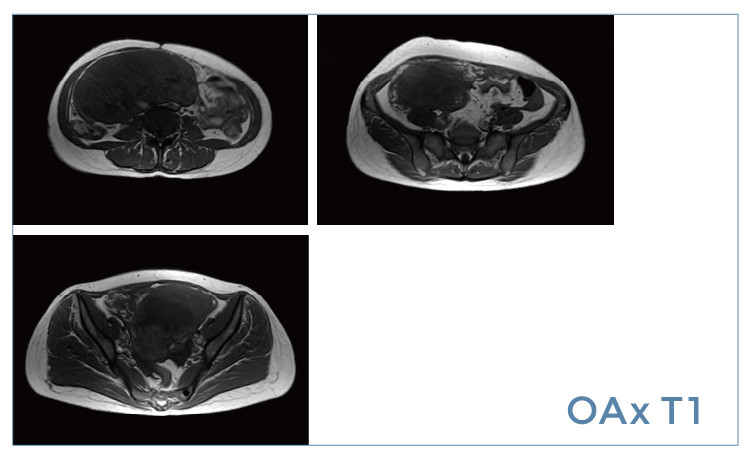

【朗润影像档案】20190405磁共振影像病例结果讨论

【朗润影像档案】磁共振影像病例分享(编号20190405)